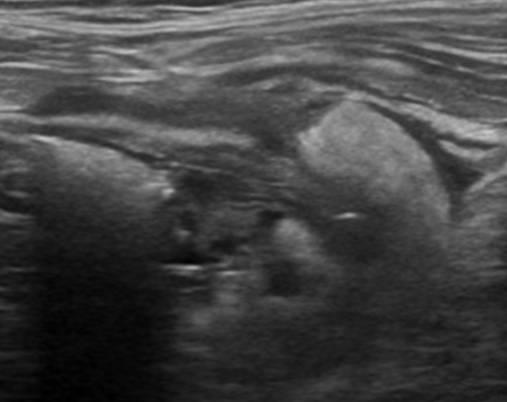

Viêm túi thừa - Ảnh 3

Viêm túi thừa

» Thông tin: Nam giới – 66 tuổi.

» Lâm sàng: Đau hố chậu trái / Sốt.